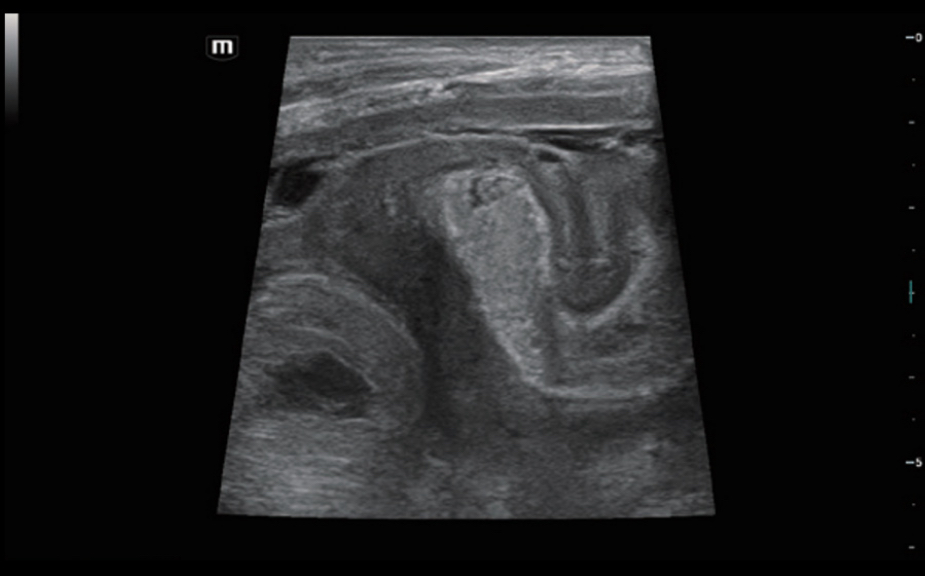

–î–Η–Α–≥–Ϋ–Ψ―¹―²–Η–Κ–Α –Ψ―΅–Α–≥–Ψ–≤―΄―Ö –Ω–Ψ―Ä–Α–Ε–Β–Ϋ–Η–Ι ―¹ –Ω–Ψ–Φ–Ψ―â―¨―é –Κ–Ψ–Ϋ―²―Ä–Α―¹―²–Ψ–≤: –Κ–Ψ–Ϋ―²―Ä–Α―¹―²-―É―¹–Η–Μ–Β–Ϋ–Ϋ–Α―è –≤–Η–Ζ―É–Α–Μ–Η–Ζ–Α―Ü–Η―è UWN+

–‰―¹–Ω–Ψ–Μ―¨–Ζ–Ψ–≤–Α–Ϋ–Η–Β –Κ–Α–Κ –≤―²–Ψ―Ä–Ψ–Ι –≥–Α―Ä–Φ–Ψ–Ϋ–Η–Κ–Η, ―²–Α–Κ –Η –Ϋ–Β–Μ–Η–Ϋ–Β–Ι–Ϋ―΄―Ö ―³―É–Ϋ–¥–Α–Φ–Β–Ϋ―²–Α–Μ―¨–Ϋ―΄―Ö ―¹–Η–≥–Ϋ–Α–Μ–Ψ–≤

–£―΄―¹–Ψ–Κ–Α―è ―΅―É–≤―¹―²–≤–Η―²–Β–Μ―¨–Ϋ–Ψ―¹―²―¨ –Κ –Ϋ–Η–Ζ–Κ–Ψ–Α–Φ–Ω–Μ–Η―²―É–¥–Ϋ―΄–Φ ―¹–Η–≥–Ϋ–Α–Μ–Α–Φ –Η –±–Ψ–Μ―¨―à–Β–Β –≤―Ä–Β–Φ―è –Ω–Β―Ä―¹–Η―¹―²–Β–Ϋ―Ü–Η–Η –Κ–Ψ–Ϋ―²―Ä–Α―¹―²–Ϋ–Ψ–≥–Ψ –≤–Β―â–Β―¹―²–≤–Α

–ö–Θ–Θ–½–‰: –Φ–Β―²–Α―¹―²–Α―²–Η―΅–Β―¹–Κ–Η–Ι ―Ä–Α–Κ –Ω–Β―΅–Β–Ϋ–Η

–ö–Θ–Θ–½–‰: –Ω–Β―Ä―³―É–Ζ–Η―è –Α–¥–Β–Ϋ–Ψ–Φ―΄ ―â–Η―²–Ψ–≤–Η–¥–Ϋ–Ψ–Ι –Ε–Β–Μ–Β–Ζ―΄